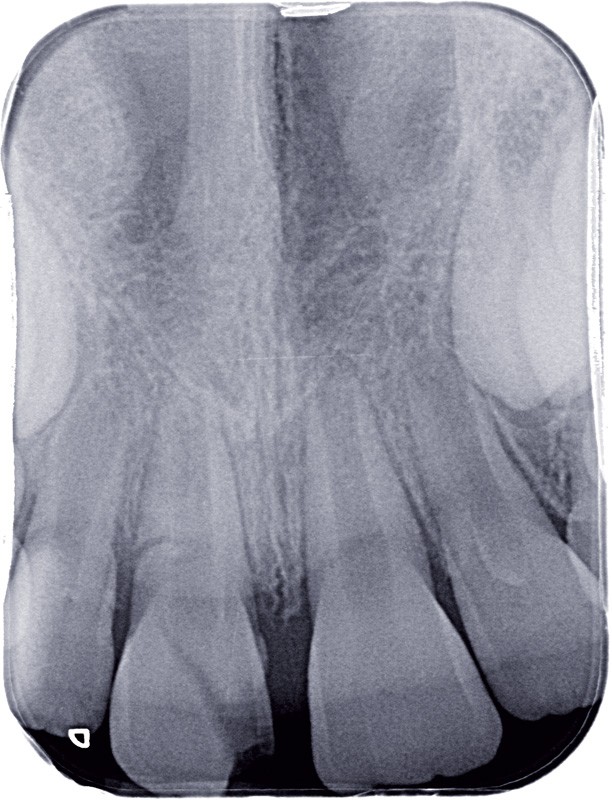

a à d Jeune patiente âgée de 8 ans, adressée suite à un traumatisme survenu 3 semaines auparavant, pour l’extraction de sa 21. La vue clinique montre un saignement ligamentaire, une mobilité coronaire et une fracture coronaire amélodentinaire longitudinale partant de l’angle mésial et se poursuivant en direction radiculaire sous-gingivale (a). Un test de vitalité positif indique que la dent est vitale, la radiographie permet de poser le diagnostic de fracture coronoradiculaire, et d’objectiver l’immaturité radiculaire (stade 8 de Nolla) (b). Une contention est mise en place et la plaie dentinaire coronaire est scellée au mieux par collage afin de limiter le risque d’une complication infectieuse (c). A 15 jours la dent est vivante et aucune complication n’est apparue (d). La patiente est revue après 3 mois pour déposer la contention, le test de vitalité est positif, et la radiographie de contrôle montre une apexogenèse en cours (e). Cependant la gencive s’est invaginée dans le trait de fracture (f). La zone est débridée sous microscope (g) puis scellée et reconstituée à l’aide d’un adhésif SAM et d’un composite fluide (h). Le contrôle radiographique à 6 mois est satisfaisant (i). Ce cas clinique illustre le fort potentiel des pulpes jeunes et du ligament alvéolodentaire à résister aux agressions et à assurer les fonctions dentinogénétiques et l’édification radiculaire.